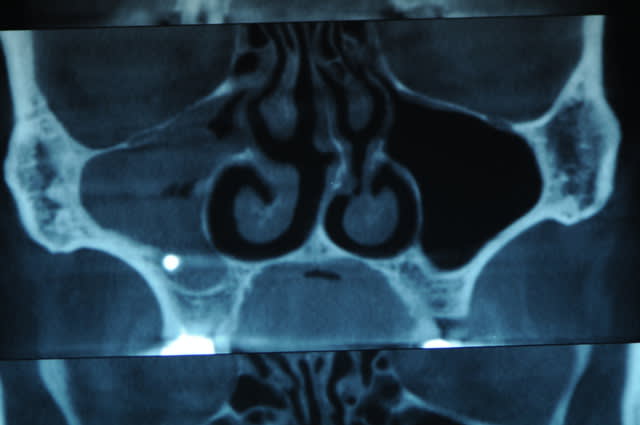

Que pensez-vous de cette bouse très radio-opaque dans le sinus maxillaire gauche ?

Pâte à canaux (un pot entier) ?

Noyau de pêche ?

Boulette de shit ?

Comblement de sinus au MTA par voie endocanalaire !

Vu la quantité, on comprends qu'il a les moyens ton patient !

> je suis pas sûr que ce soit DANS le sinus... en vestibulaire?

Pas dans la bouche en tout cas.